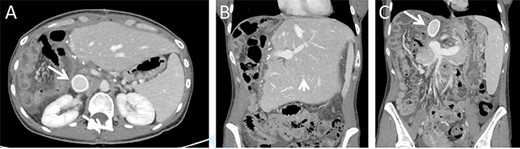

A previously healthy 38-year-old woman presented with a subacute one-month increase of a four-year slowly progressive right sided abdominal and back pain. Ten months prior to her visit she gave birth to a healthy child following an uneventful pregnancy. One month prior to her presentation, blood tests were taken as part of routine evaluation prior to in-vitro fertilization treatments that showed elevated serum hepatocellular enzymes. At the time of her admission an ultrasound was performed revealing an enlarged liver with a non-homogeneous echogenic structure in the right lobe, compressing the portal system. In light of these results and increasing pain she was referred to the emergency department. Upon her arrival her vital signs were normal. Physical examination revealed a large mass, slightly tender to palpation, in the right upper abdominal quadrant. Laboratory blood indices demonstrated a normal blood count, slight elevation of hepatocellular enzymes (ALT = 52, AST = 46) and cholestatic enzymes (GGT = 219, ALP = 435). Bilirubin levels were normal. The CA15.3 tumour marker was elevated (50.1 IU/ml). All other tumour markers including CEA, CA19–9, CA125, and AFP remained within normal limits. Abdominal computed tomography (CT) and magnetic resonance imaging demonstrated a 14.5x12x15cm mass in the right hepatic lobe causing mass effect on adjacent abdominal and retroperitoneal organs, and involving the retrohepatic IVC (Fig. 1). No signs of biliary obstruction were seen.

Preoperative CT and MR imaging. Axial (A + B) and coronal (C + D) CT images depicting a large mass replacing the right liver lobe, involving the retrohepratic IVC and compressing the right kidney. The portal bifurcation is free of tumour and the left portal vein is patent. (E + F) MR images depicting the large lesion occupying the right liver lobe and involving the retrohepatic IVC.